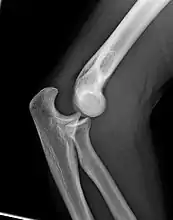

The elbow is the region between the upper arm and the forearm that surrounds the elbow joint.[1] The elbow includes prominent landmarks such as the olecranon, the cubital fossa (also called the chelidon, or the elbow pit), and the lateral and the medial epicondyles of the humerus. The elbow joint is a hinge joint between the arm and the forearm;[2] more specifically between the humerus in the upper arm and the radius and ulna in the forearm which allows the forearm and hand to be moved towards and away from the body.[3][4] The term elbow is specifically used for humans and other primates, and in other vertebrates forelimb plus joint is used.[1]

When in anatomical position there are four main bony landmarks of the elbow. At the lower part of the humerus are the medial and lateral epicondyles, on the side closest to the body (medial) and on the side away from the body (lateral) surfaces. The third landmark is the olecranon found at the head of the ulna. These lie on a horizontal line called the Hueter line. When the elbow is flexed, they form a triangle called the Hueter triangle, which resembles an equilateral triangle.[5]

At the surface of the humerus where it faces the joint is the trochlea. In most people, the groove running across the trochlea is vertical on the anterior side but it spirals off on the posterior side. This results in the forearm being aligned to the upper arm during flexion, but forming an angle to the upper arm during extension — an angle known as the carrying angle.[6]